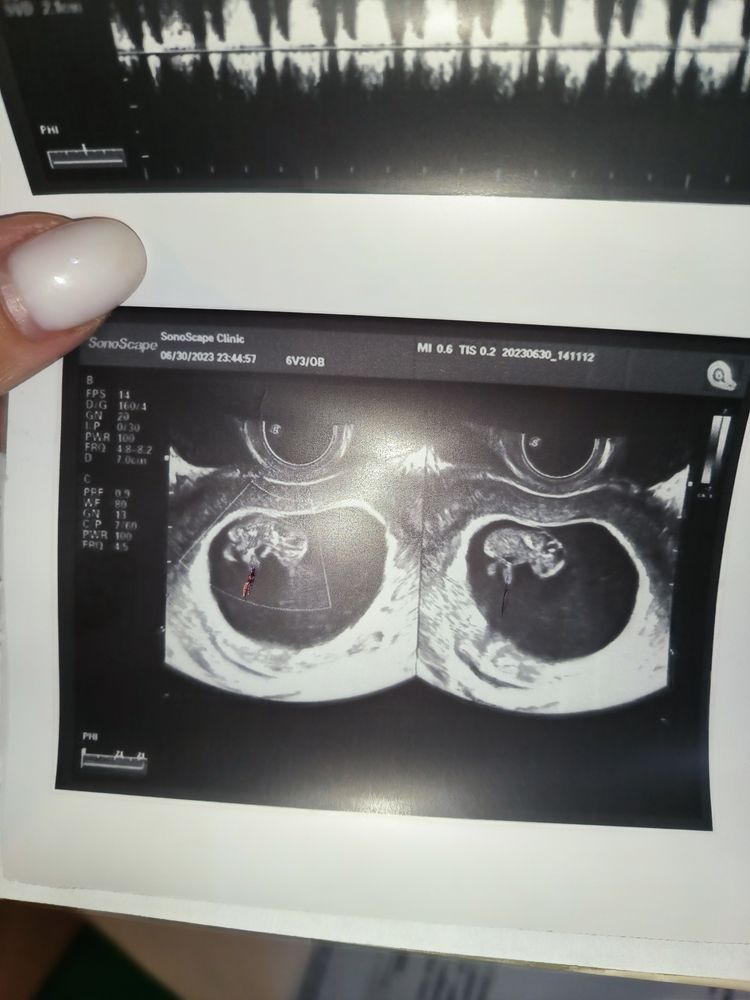

Poppiholla, теперь я вообще ничего не понимаю) съездила к тому же врачу который двойню увидел, вот ее новое заключение, на фото она ручкой отметила, это не может быть пуповиной,или блин просто ногой ребенка?🙄